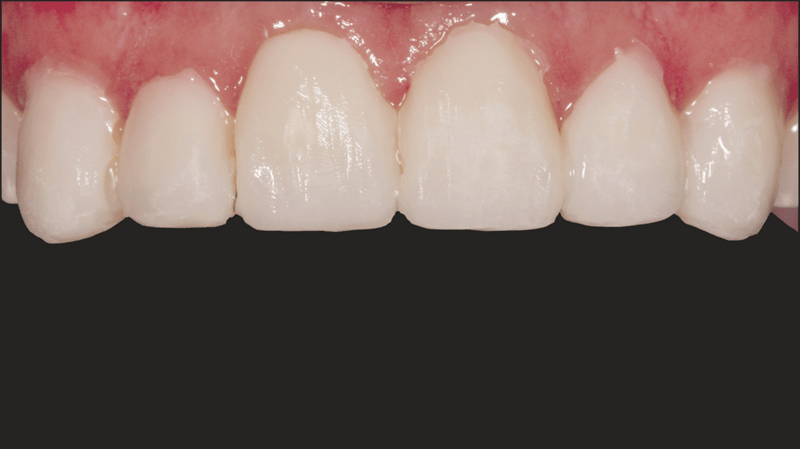

- Finale Restauration: Endgültige Zementierung mit einer stabilen und ästhetisch ansprechenden Veneer-Versorgung.

Mit dem durchgeführten Behandlungsprotokoll konnten die ästhetischen Anforderungen der Patientin erfüllt werden. Die Verfärbung der oberen Frontzähne wurde kaschiert und ein natürliches, auf die unteren Frontzähne abgestimmtes, Erscheinungsbild wurde erzielt. Die Verwendung von direkten Non-Prep-Kompositveneers war dabei eine konservative, höchst effektive Lösung, die sowohl den finanziellen Möglichkeiten der Patientin als auch ihrem Wunsch nach minimal-invasiven Methoden Rechnung trug.

- Komposit-Applikation: Applikation von Transcend Komposit (Farbe B1D ), beginnend mit einem 2/3 Abstand von der Inzisalkante. Allmähliche Ausdünnung in Richtung Gingiva. Applikation der Farbe „Universal Body“ (UB) nahe des gingivalen Drittels. Auftragen der finalen Schichten mit Enamel White (EW) und einer kleinen Menge UB am gingivalen Rand, um einen natürlichen Farbverlauf zu erzielen.